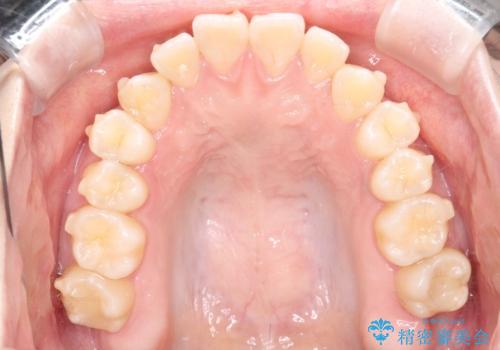

【インビザライン】歯を抜かずにできるだけ前歯を下げたい

- 前歯の前突を主訴に来院されました。

インビザライン を用いて、歯並びの改善を行うことができました。